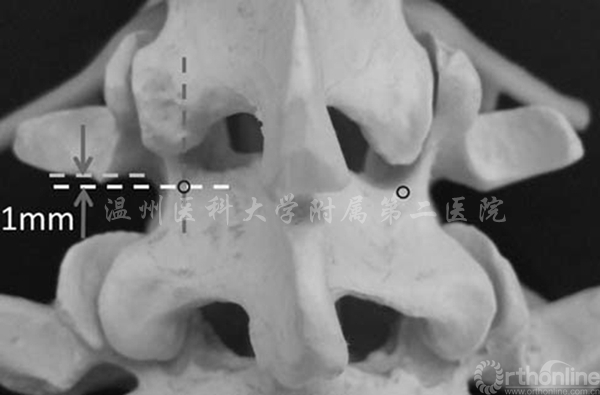

Ivanov等人发现峡部的厚度从内侧至外侧边缘逐渐增加,而进针点选择在为上关节突中线与横突下1mm之间的交点,大致位于峡部外侧缘向内3mm左右,正好位于椎体背侧皮质骨且接近峡部外侧处(2)[3]

图2 进针点(圆圈标记)为上关节突中心与横突下缘1mm的交点(相当于峡部外侧壁内3mm处)